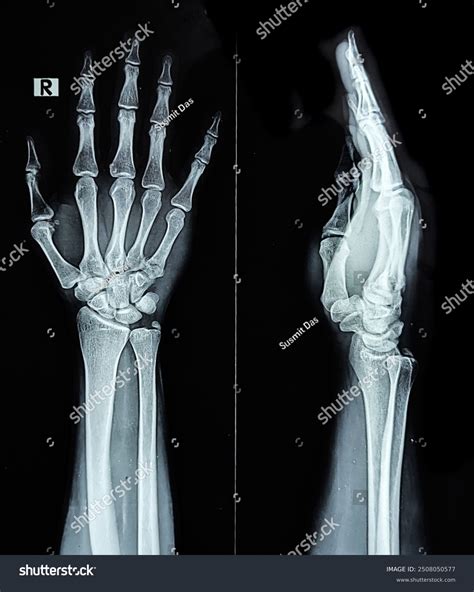

The Wrist Bones Xray procedure is typically quick and painless. Here is what you can expect during the process:

• Positioning: You will be asked to sit or stand with your wrist and hand positioned on a special table. The technician will adjust the position to ensure the best possible view of the wrist bones.

• Exposure: The technician will step behind a protective barrier and activate the X-ray machine. You will feel a brief flash of light as the X-ray is taken.

• Multiple Views: Several X-ray images may be taken from different angles to provide a comprehensive view of the wrist bones and joints.

Interpreting Wrist Bones Xray Results

Interpreting the results of a Wrist Bones Xray requires the expertise of a radiologist or orthopedic specialist. The images will be reviewed to identify any abnormalities or injuries. Some common findings on a wrist X-ray include: